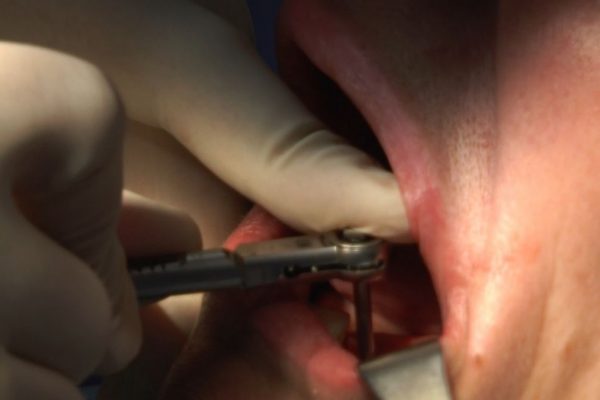

W ostatni weekend czerwca 2018 roku kursanci II Sezonu Preludium Implantologii odbyli piątą, finałową sesję, która w całości podporządkowana była praktyce. W ciągu dwóch dni zabiegowych Lekarze uczestniczący w szkoleniu przeprowadzili szereg zabiegów pod kierunkiem dr n.med. Violetty Szycik. Wszczepili 17 implantów oraz przeprowadzili ekstrakcje i zabiegi regeneracyjne kości. Zabiegi były wykonywane także w sedacji dożylnej z udziałem specjalisty anestezjologii i intensywnej terapii dr Jolanty Grzybowskiej. Preludium implantologii to nowy program edukacyjny dla adeptów implantologii stomatologicznej, którego celem jest wprowadzenie do implantologii poprzez pozyskanie wiedzy w szerokim zakresie i uwzględnieniem szczegółów mających decydujące znaczenie dla powodzenia leczenia implantologicznego. Ale tak jak wszystkie szkolenia w Instytucie Vivadental, w tym wiodące Practiculum Implantologii, zorientowane jest na praktyce i samodzielnym wykonywaniu zabiegów pod kierunkiem Mentora. To najlepsza edukacja w medycynie zabiegowej, a zarazem najlepszy start do implantologii.